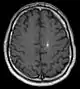

Diagnosis is generally made by magnetic resonance imaging (MRI), particularly using a specific imaging technique known as a gradient-echo sequence MRI, which can unmask small or punctate lesions that may otherwise remain undetected. These lesions are also more conspicuous on FLAIR imaging compared to standard T2 weighing. FLAIR imaging is different from gradient sequences. Rather, it is similar to T2 weighing but suppresses free-flowing fluid signal. Sometimes quiescent CCMs can be revealed as incidental findings during MRI exams ordered for other reasons. Many cavernous hemangiomas are detected "accidentally" during MRIs searching for other pathologies. These "incidentalomas" are generally asymptomatic. In the case of hemorrhage, however, a CT scan is more efficient at showing new blood than an MRI, and when brain hemorrhage is suspected, a CT scan may be ordered first, followed by an MRI to confirm the type of lesion that has bled.[12] Sometimes the lesion appearance imaged by MRI remains inconclusive. Consequently, neurosurgeons will order a cerebral angiogram or magnetic resonance angiogram (MRA). Since CCMs are low flow lesions (they are hooked into the venous side of the circulatory system), they will be angiographically occult (invisible). If a lesion is discernible via angiogram in the same location as in the MRI, then an arteriovenous malformation (AVM) becomes the primary concern.